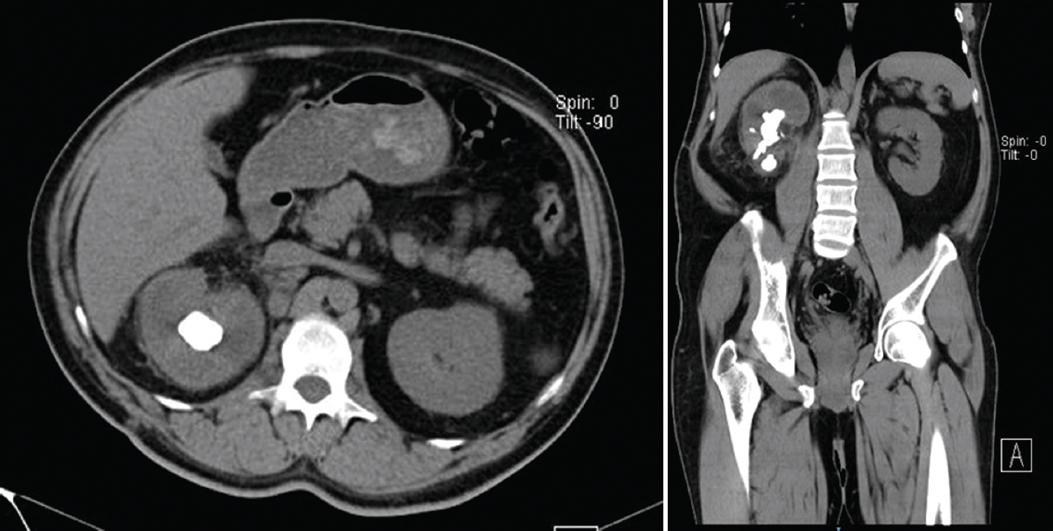

En las figuras 2 y 3 se ilustra un caso representativo de los 51 pacientes con PE, incluyendo hallazgos tomográficos.

Figura 3 Caso del mismo paciente de la figura 2 posterior a tratamiento con carbapenémico más colocación percutánea de catéter de 10 Fr de nefrostomía derecha y pielografía percutánea. Tras 14 días de estancia fue egresado por mejoría. La tomografía computada abdominopélvica simple muestra una imagen hiperdensa de aproximadamente 30 × 20 mm y 1045 UH, con presencia de hidronefrosis homolateral leve y riñón contralateral sin alteraciones. Se observa disminución del gas en el parénquima y el sistema colector, con ausencia de niveles hidroaéreos respecto a la tomografía previa.